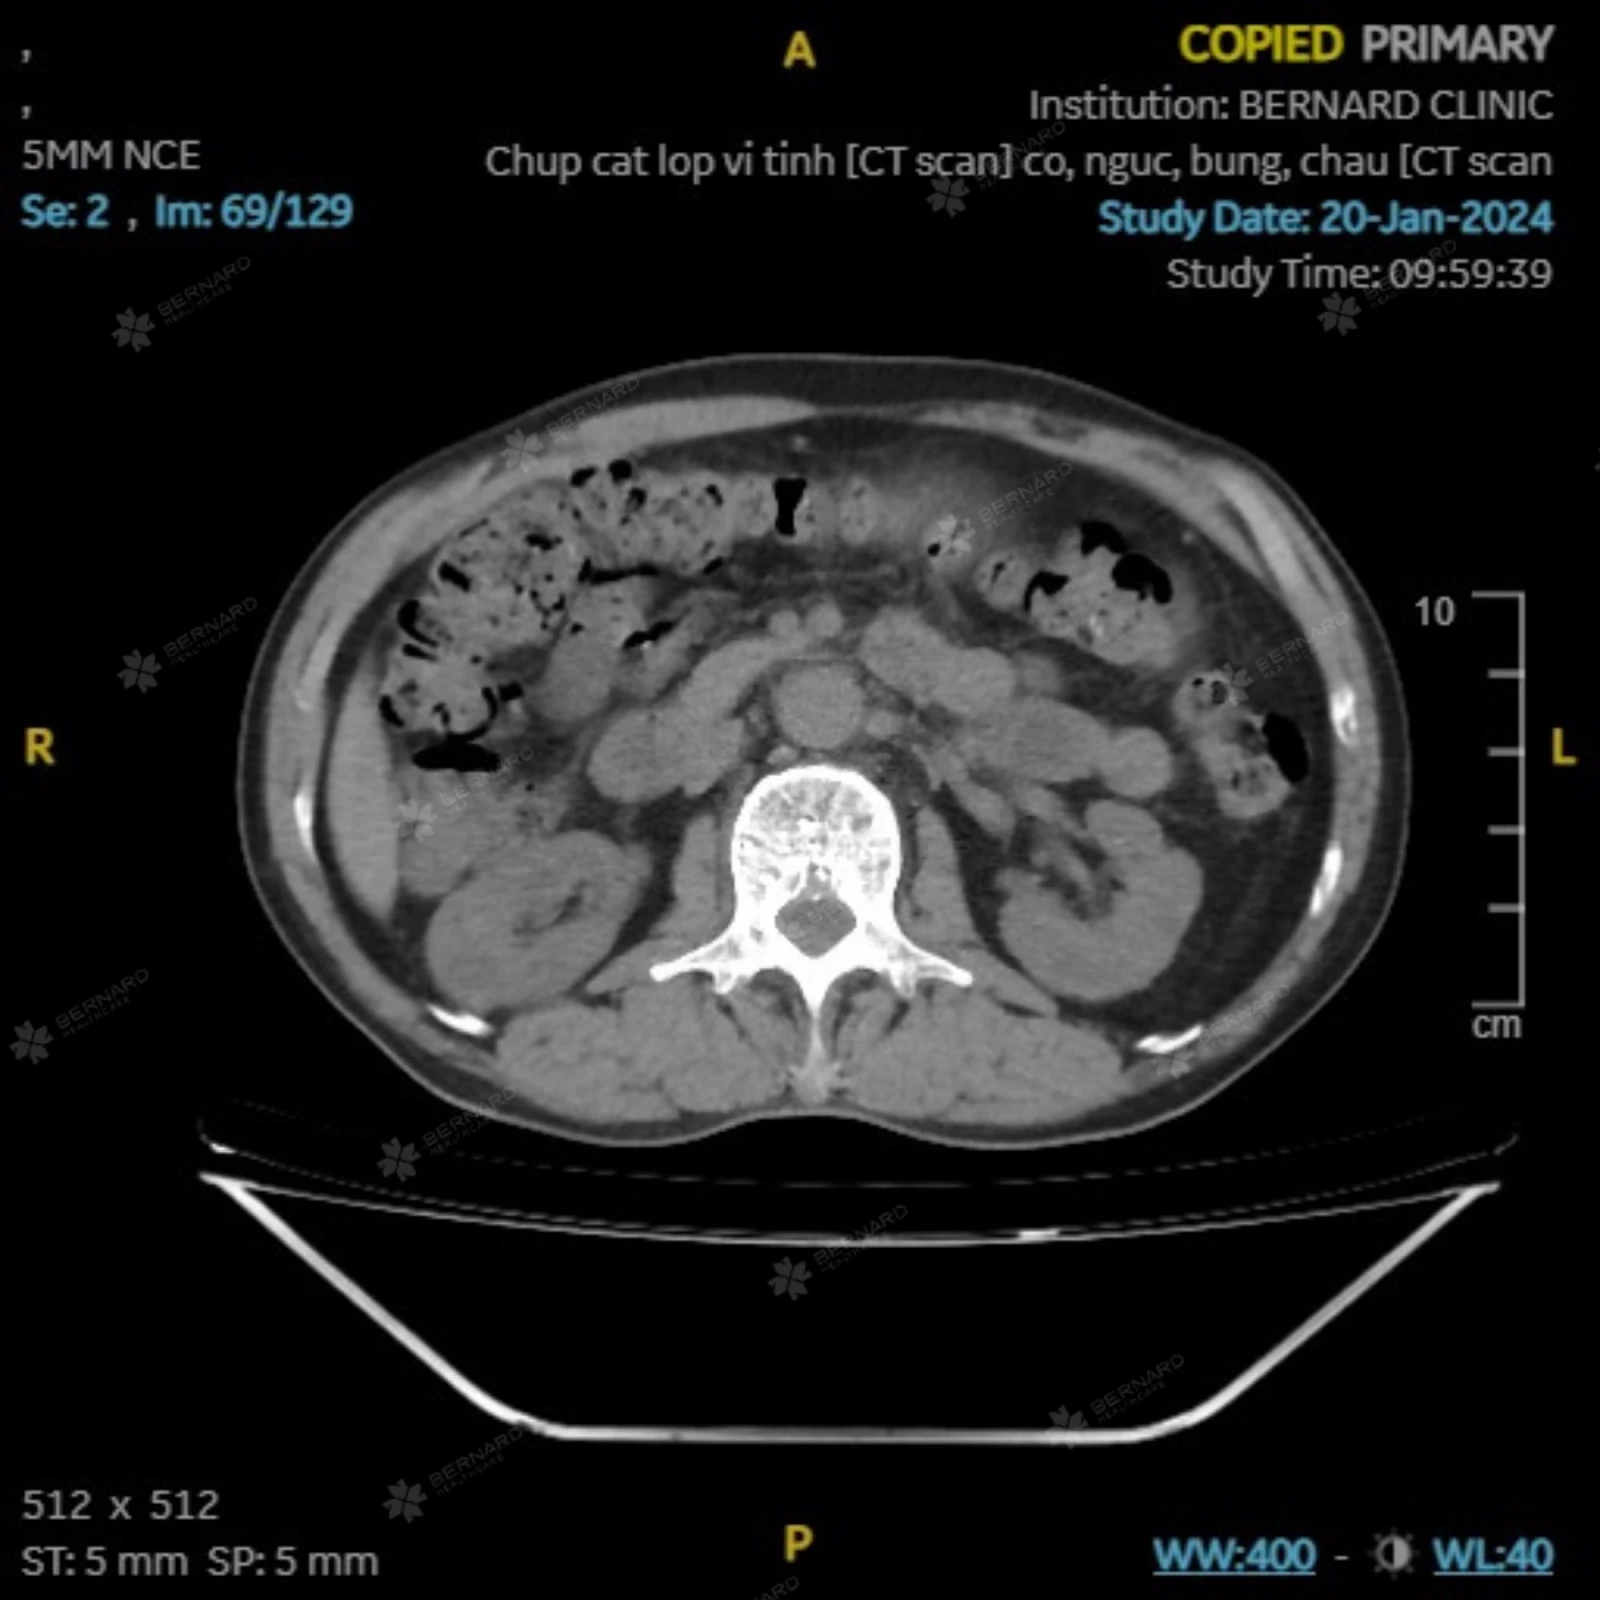

Theo các hạng mục trong khuôn khổ gói khám, ông S. được thực hiện chụp cắt lớp vi tính - CT Scan. Hình ảnh lớp cắt qua khu vực bụng - chậu phát hiện có tình trạng dày thành đại tràng sigma, d #7mm, chiều dài #2.5cm.